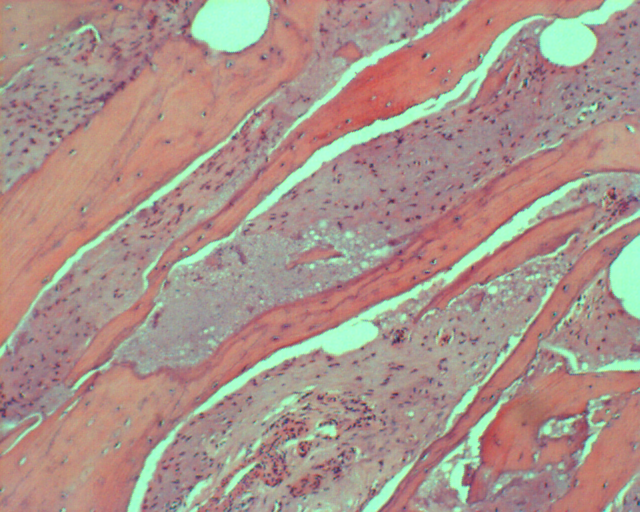

2.髓内高分化骨肉瘤(Intraosseous well-differentiated osteosarcoma)

髓内高分化骨肉瘤又称中心性低恶度骨肉瘤(central low-grade osteosarcoma),较少见,约占骨肉瘤的1%。发病年龄较普通骨肉瘤大,女性多见。其组织学特点及生物学行为类似于骨旁骨肉瘤,但病变发生于长骨髓腔内,随病情进展可突破骨皮质向外生长,并压迫或包绕主要神经、血管。

4、病例4:女 58岁 右肱骨中上段髓内高分化骨肉瘤,行瘤段广泛切除异体半关节移植术

图 25 组织学特点:纤维性间质,产生胶元的梭形细胞交织排列,数量不等的骨样基质,成骨细胞有一定异型,肿瘤形成较多层状骨。